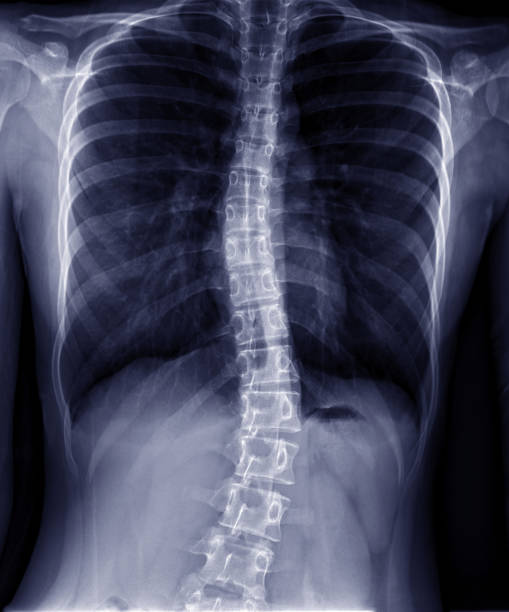

Skolyoz, omurganın yalnızca yana doğru eğilmesiyle sınırlı olmayan, aynı zamanda omurların kendi ekseni etrafında dönmesiyle birlikte ortaya çıkan üç boyutlu bir omurga deformitesidir. En sık çocukluk ve ergenlik döneminde fark edilir, duruş bozukluğundan farklı olarak irade ile düzeltilemez, hafif vakalar fark edilmeden kalabilirken ilerleyen eğrilikler omuz, kürek kemiği ve bel asimetrisine, ileri durumlarda ise ağrıya, solunum kapasitesinde azalmaya ve yaşam kalitesinde düşüşe yol açabilir. Bu nedenle erken tanı ve düzenli takip skolyoz yönetiminde temel öneme sahiptir.

Adolesanlarda görülen ve omurga eğriliğinin 30 derecenin üzerine çıktığı skolyoz vakaları kızlarda erkeklere göre yaklaşık 10 kat daha sık görülmektedir. Bunun nedeni tek bir faktöre bağlanamaz. Bu fark, biyolojik, hormonal, gelişimsel ve hatta tanısal bazı etkenlerin bir araya gelmesiyle ortaya çıkar ve özellikle ergenlik döneminin vücut üzerindeki hızlı ve dengesiz değişimleri bu tabloyu belirginleştirir.

Bir diğer önemli nokta ise skolyozun fark edilme ve ilerleme biçimidir. Kızlarda eğrilikler estetik olarak daha erken fark edilir ve ilerleme eğilimi daha yüksek olduğu için 30 derece üzeri vakalar istatistiklere daha sık yansır, bu da kızlarda skolyozun hem daha görünür hem de daha ciddi seyretmesine neden olur. Bu yüzden erken tanı, düzenli takip ve büyüme dönemi boyunca yapılan kontroller, özellikle kız çocuklarında skolyozun ilerlemesini durdurmak ve cerrahiye gidişi önlemek açısından hayati önem taşır.